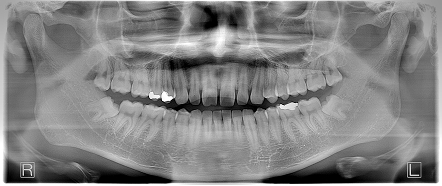

上顎中切歯の歯間離開 【20代・男性】

治療前後の比較

Before

before1枚目before2枚目